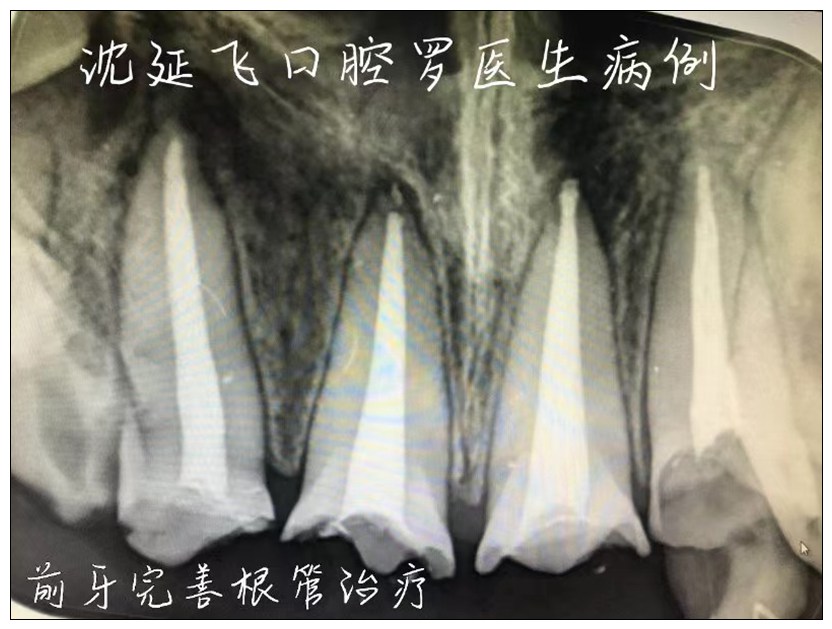

沈延飞口腔

凤城沈延飞口腔门诊部

服务宗旨:用心服务,精益求精。

愿成为您一生的保健牙医